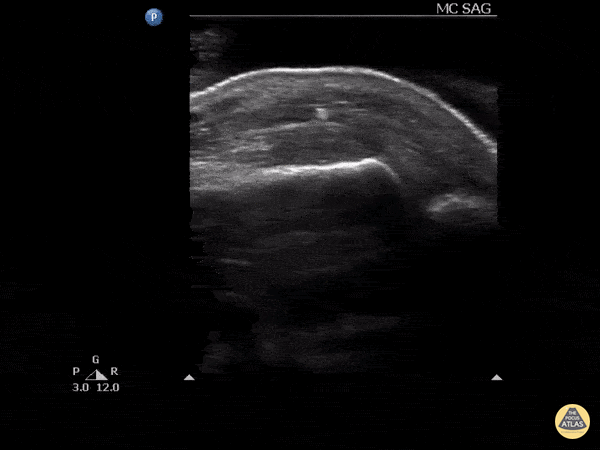

Trauma - Foreign body: glass

Pictured here is a retained glass piece as result of a closed fist injury with a window Image courtesy of Robert Jones DO, FACEP @RJonesSonoEM Director, Emergency Ultrasound; MetroHealth Medical Center; Professor, Case Western Reserve Medical School, Cleveland, OH View his original post here